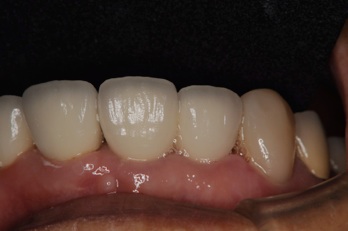

こうなるとそれに差し歯を被せれば

歯の長持ち度が全然違います

なんとか綺麗な歯が入りました。最初に歯が折れた時も差し歯はグラスファイバーの土台をいれていたので、根っ子が折れずに使えたと思います。これが保険の銀合金の硬い土台だったなら根っ子ごと折れて抜歯になっていたでしょう。